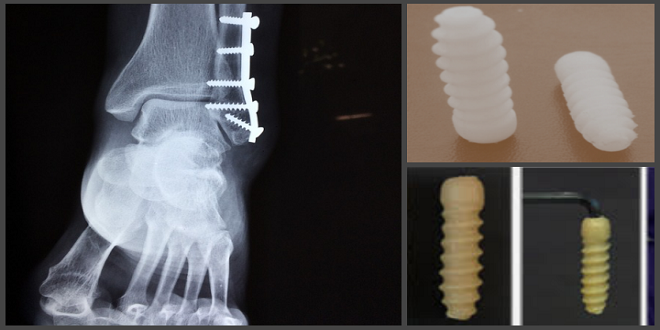

أعلن فريق بحثي روسي عن ابتكار مسامير عظمية قابلة للتحلل الحيوي، تمثل بديلاً أكثر أماناً وتوافقاً مع الجسم، مقارنة بالمسامير المعدنية المستخدمة حالياً في جراحات العظام.

وأظهرت الدراسة أن المسامير الجديدة المصنوعة من مادة البولي لاكتيد والمغطاة بطبقات حيوية تشمل الكولاجين والنانو هيدروكسي أباتيت، ساهمت في تحسين اندماج العظم وتقليل الالتهابات والعدوى، مع إمكانية إضافة أسلاك فضية نانوية لتعزيز الخصائص المضادة للبكتيريا.

وأظهرت التجارب المخبرية قدرة المسامير على تعزيز التصاق الخلايا العظمية ونموها بسرعة، مع انخفاض عدد الخلايا الالتهابية وزيادة نشاط الخلايا البانية، للحد من المضاعفات وتسريع التئام العظام، ما يؤكد فعالية الطلاءات الحيوية المطورة.

ويأمل الباحثون أن يفتح هذا الابتكار الباب أمام تطبيقات سريرية جديدة تقلل الحاجة إلى عمليات جراحية لاحقة، وتوفر خيارات أكثر أماناً وفعالية لعلاج كسور العظام والزرعات المعدنية التقليدية.